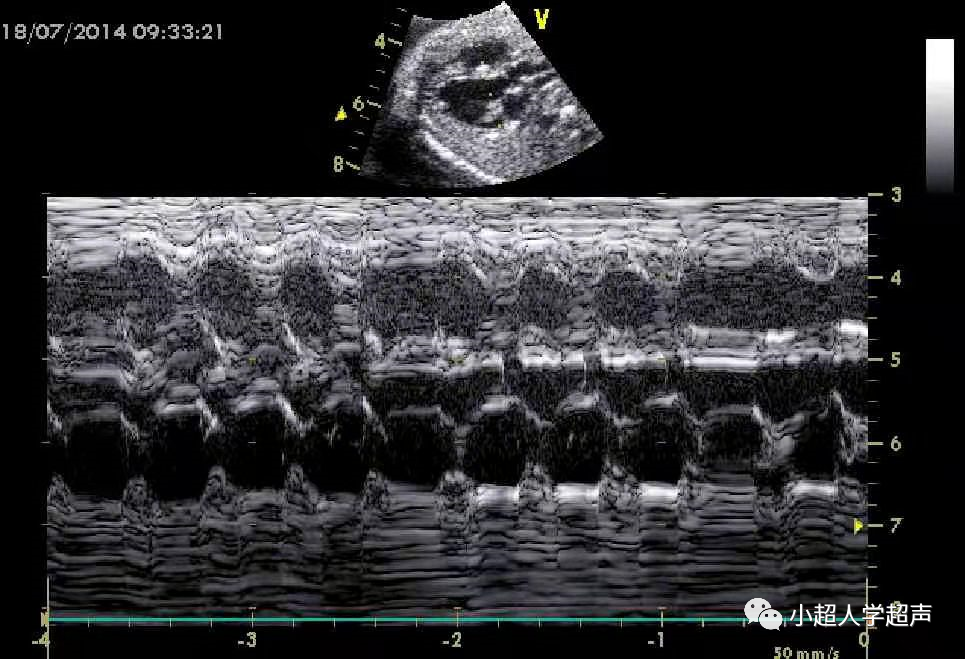

(2)二度房室传导阻滞

① 二度Ⅰ型房室传导阻滞是M型超声或频谱多普勒A-V间距进行性延长,并脱落后(心房波漏搏一次),房室传导周期性中断后,再重复。

(为短-长-更长-掉)